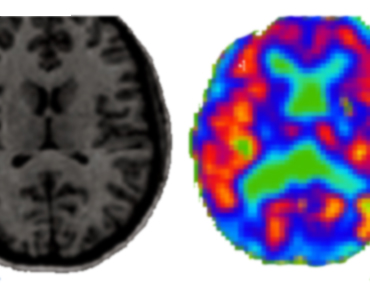

病理模型库及病变分割

多病理诊断

图像识别、深度学习建立算法与病理数据的接入分析

多模态数据包、开展模型对数据集包的批量式训练